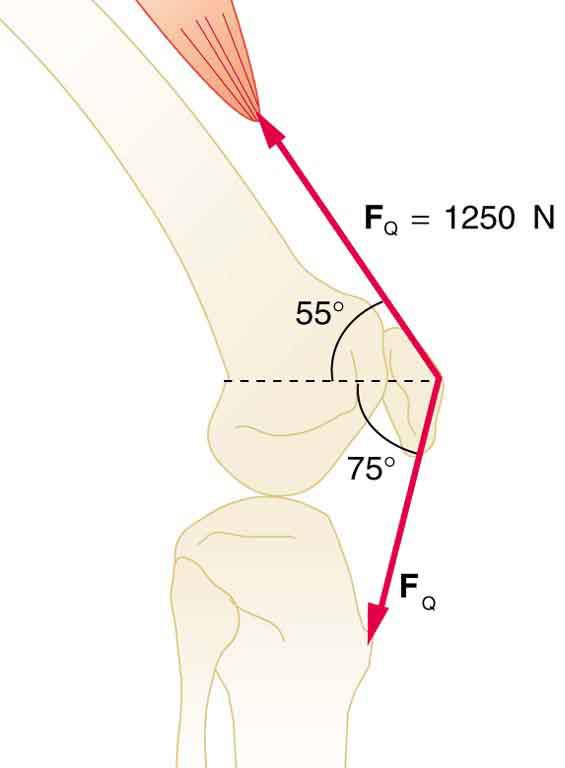

The upper leg muscle (quadriceps) exerts a force of 1,250 N, which is carried by a tendon over the kneecap (the patella) at the angles shown in Figure 9.39. Find the direction and magnitude of the force exerted by the kneecap on the upper leg bone (the femur).